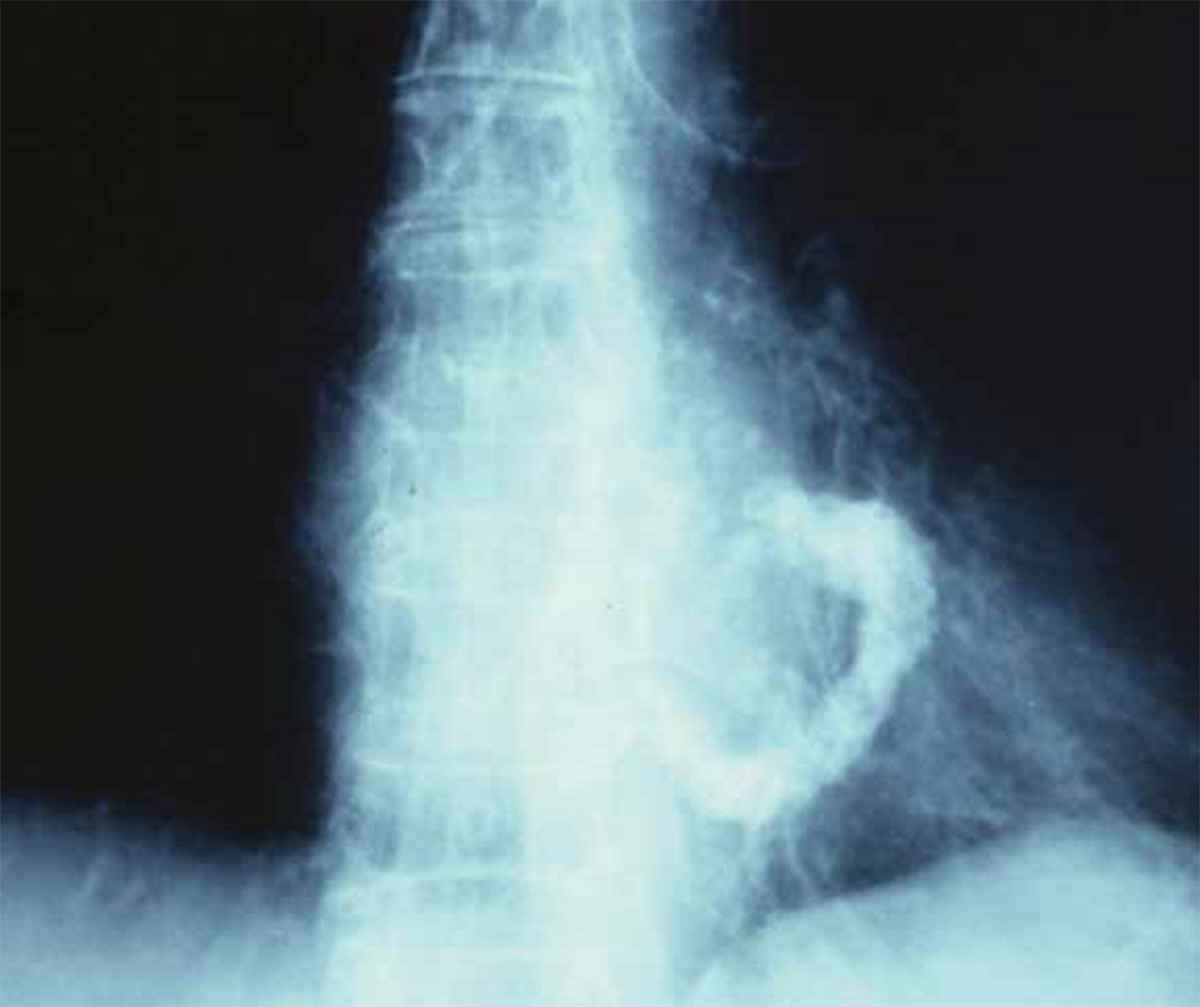

Quel est votre diagnostic ?

Il s'agit de la calcification de l'anneau mitral. Les calcifications valvulaires, ou annulaires, se retrouvent dans les valvulopathies mitrales d'origine rhumatismales ou dégénératives. Avec le déclin du rhumatisme articulaire aigu, les valvulopathies rhumatismales sont devenues rares, contrairement à celles dites « dégénératives » dont la fréquence augmente avec l'âge. L'insuffisance mitrale rhumatismale est rarement isolée ; elle est associée dans 90 % des cas à une sténose mitrale. Elle est secondaire à la rigidité de l'orifice mitral, qui reste figé en diastole et en systole. Quant aux insuffisances mitrales dégénératives, elles sont caractérisées par des élongations ou ruptures de cordages et des anomalies de tissu valvulaire et peuvent être séparées en deux groupes : la maladie de Barlow et la dégénérescence fibroélastique. Le rétrécissement dégénératif survient quasi exclusivement chez les sujets âgés. Il est lié à un engainement calcaire progressif de la valve mitrale, alors que les commissures restent indemnes et ouvertes, à la différence du rétrécissement rhumatismal calcifié. Les dépôts calciques débutent au niveau de l'anneau et de la base des valves et s'étendent progressivement vers leurs extrémités. Il pose un problème thérapeutique, car les options sont limitées : la dilatation mitrale percutanée n'est pas indiquée, les commissures étant ouvertes. La chirurgie est très complexe du fait de l'importance des calcifications. Le plus souvent, un traitement médical symptomatique est recommandé.